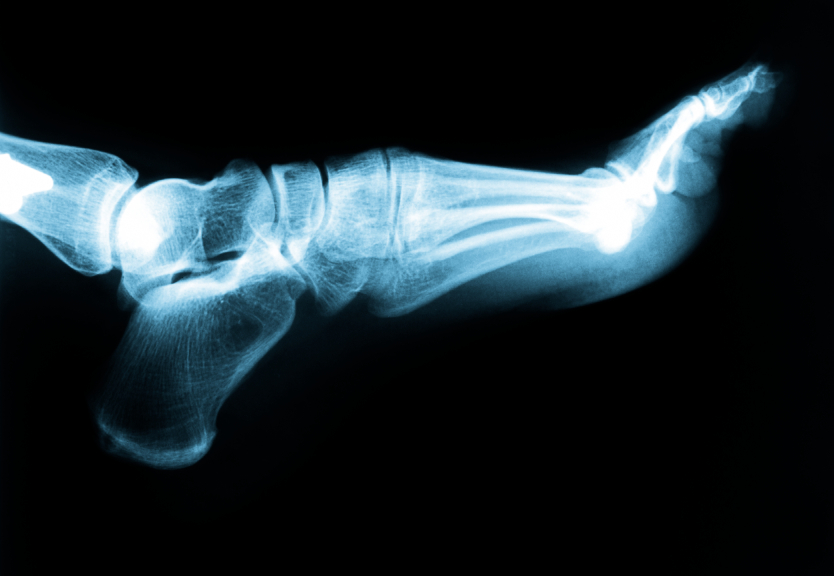

When individuals begin to experience intense pain in their heel, many know that they have acquired plantar fasciitis. This ailment occurs when the plantar fascia ligament along the bottom of the foot develops tears in the tissue. This will result in pain and inflammation of the area closest to the heel bone.

The fascia ligament tightens up over night and therefore causes the most pain in the morning. Pain generally decreases as the tissue warms up, but oftentimes returns after long periods of standing or weight bearing and physical activity.